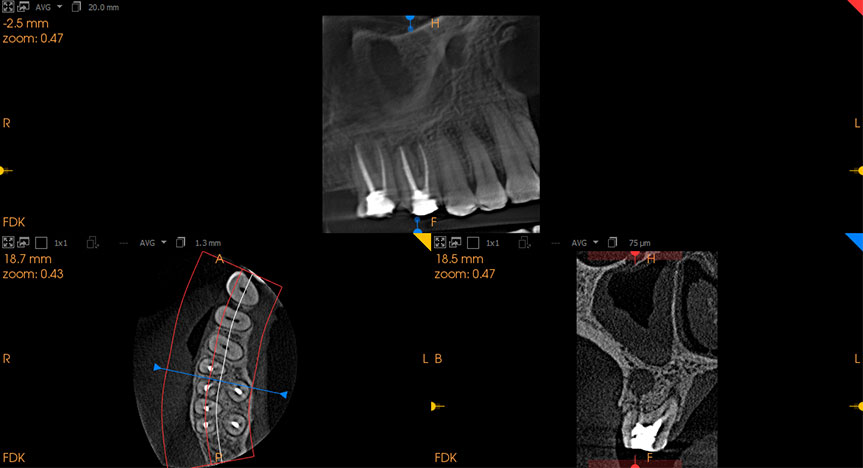

Our dental clinic is also equipped with an in-house cone beam CT machine. This additional 3-dimensional imaging tool can detect hidden anatomy and findings not visible in conventional x-rays. This further enhances the precision of your root canal treatment.